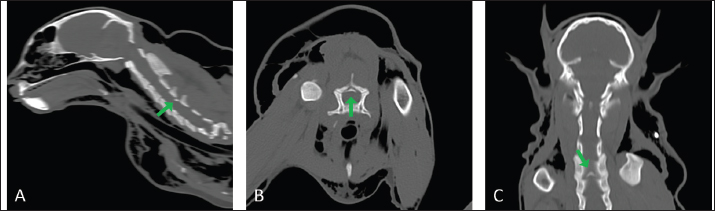

Fig. 1. Thoracic radiography (lateral view) performed upon patient arrival. Note the severe subcutaneous emphysema (white asterisk) in the head and neck region combined with moderate pneumomediastinum and mild pneumothorax.

Fig. 3. Longitudinal (A, C) and transverse (B) CT images acquired with the cat placed in the VetMouse TrapTM. Incomplete fracture line of the caudal margin of the fourth cervical vertebral arch (green arrow). The fragment is dislocated into the vertebral canal, narrowing the dorsoventral diameter with subsequent compression of the spinal cord.